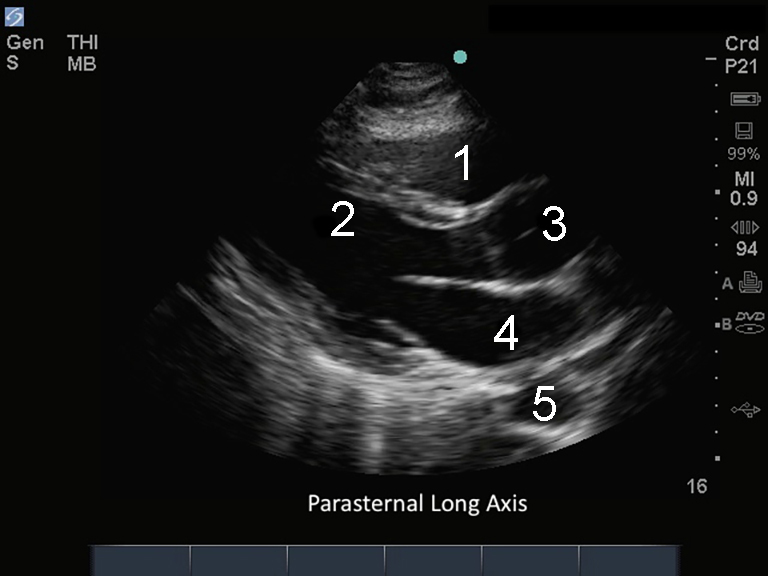

M-Turbo: 傍胸骨長軸

右心室 (RV)

左心室(LV)

上行大動脈(Ao)

左心房(LA)

下行大動脈(Ao)